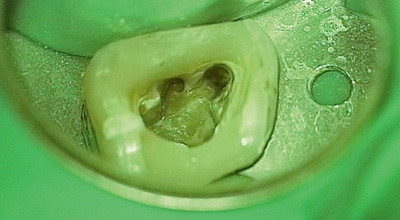

Zunächst wurden die insuffiziente Amalgamfüllung und die Sekundärkaries entfernt und der Zahn mit einer Kompositfüllung (Ceram X™ Mono, Dentsply DeTrey) aufgebaut. Es folgte die Darstellung von zunächst drei Wurzelkanaleingängen. Die Entfernung der infizierten Wurzelkanalfüllung aus dem palatinalen Wurzelkanal mittels Hedströmfeilen erwies sich als einfach. Die Beseitigung der Dentinüberhänge im Bereich des distalen Wurzelkanals mit diamantierten Ultraschallansätzen (Varios Ultraschall-Aufsätze, NSK Europe GmbH) machte die vollständige Erschließung des sehr engen Kanals auf die endometrisch bestimmte Arbeitslänge möglich. Aus dem mesio-bukkalen Wurzelkanal wurde in zwei Teilen unter Einsatz des Operationsmikroskopes und der Verwendung von diamantierten Ultraschallansätzen das ca. 8mm lange Instrumentenfragment entfernt (Abb. 2). Die weitere Instrumentierung bis in den apikalen Bereich der Wurzel gestaltete sich jedoch als schwierig. Es lag eine Stufe (Ledge) vor und der apikale Kanalanteil war offensichtlich durch Dentinspäne verbolzt. Danach erfolgt die Darstellung des mesio-bukkalen Wurzelkanals und dessen vollständige Aufbereitung. Die Verläufe der Wurzelkanäle wurden röntgenologisch durch Nadelmessaufnahmen (Abb. 3 und 4) überprüft. Beide mesialen Kanäle konfluieren im Bereich des Überganges vom mittleren zum apikalen Drittel. Sie entsprechen damit Typ II der Wurzelkanalkonfiguration. Die kombiniert manuell-rotierende Aufbereitung (K-Flexofile, ProTaper®, Dentsply Maillefer) wurde durch Anwendung von 2%iger CHX sowie 20%iger EDTA-Lösung unterstützt (Abb. 5 und 6). Nach Kontrolle des korrekten Sitzes der Guttaperchaspitzen erfolgte die Wurzelkanalfüllung mittels ­lateraler Kondensationstechnik (Sealer: AH Plus™, Dentsply DeTrey). Die ­Kanaleingänge wurden mit nicht röntgenopakem Versiegelungsmaterial

auf Kompositbasis (CoroSeal, Ivoclar Vivadent) verschlossen (Abb. 7), die ­Zugangskavität mit Komposit (Ceram X™ Mono/Dentsply DeTrey) gefüllt und eine postendodontische Röntgenkontrolle durchgeführt (Abb. 8).